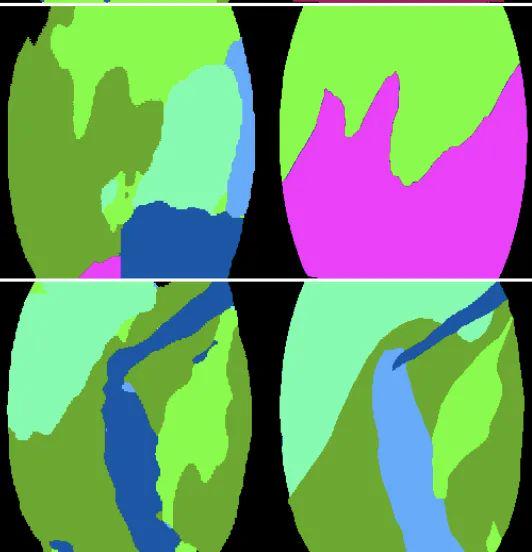

FASCICLE 小腿肌肉超声数据集

数据集链接:http://m6z.cn/631rex

FAscicle 小腿肌肉超声数据集是一个由 812 幅小腿肌肉超声图像组成的数据集,用于分析肌肉弱点并预防受伤。该数据集在文章 AW-Net:B 型超声图像上的自动肌肉结构分析以预防伤害中进行了介绍。它结合了由 Ryan Cunningham 等人发表的两篇文章“使用卷积、残差和反卷积神经网络从 B 模式超声图像中估计全区域骨骼肌纤维方向”提供的数据集。和 Neil Cronin 发表的“使用深度学习对肌肉骨骼超声图像进行自动分析”,并附有补充注释。

该 zip 文件包含两个数据集,分别分为两个由其作者命名的文件夹。每个数据集的每个图像都有一个匹配的分束分割掩码和一个可按名称识别的腱膜分割掩码。